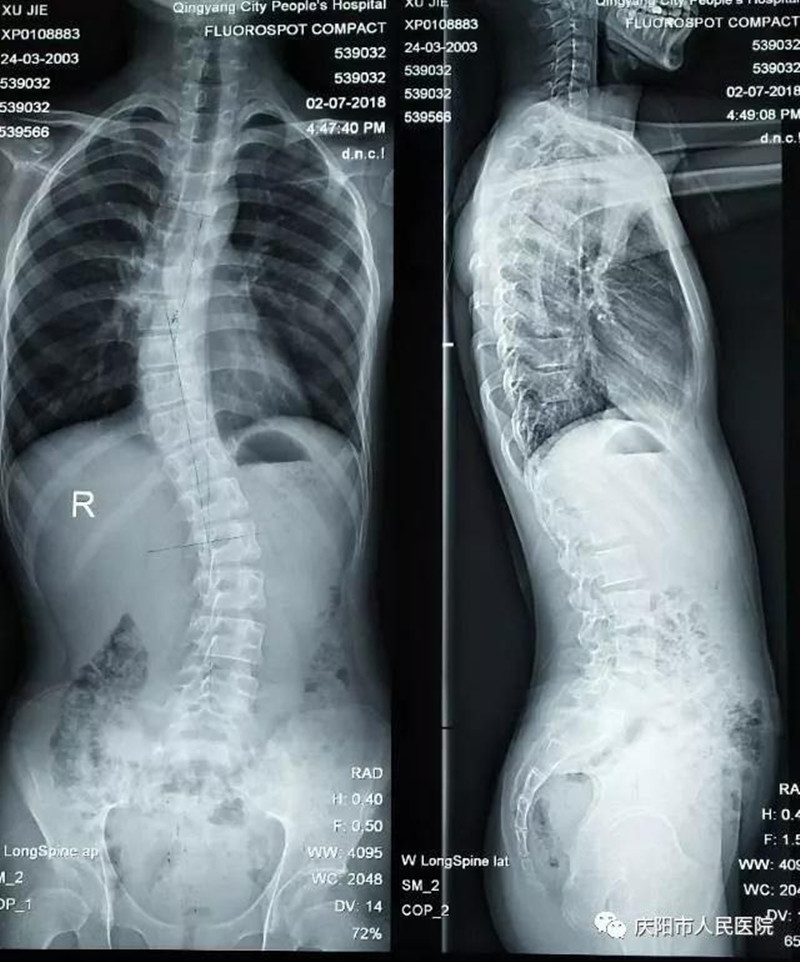

特發(fā)性脊柱側(cè)凸畸形矯形手術(shù)成功實施。脊柱側(cè)凸俗稱脊柱側(cè)彎,是一種脊柱的三維畸形,包括冠狀位、矢狀位和軸位上的序列異常,這是繼脊柱后凸畸形矯形手術(shù)開展以來,我院骨一科在脊柱外科領(lǐng)域的又一項成就,標(biāo)志著我院脊柱外科技術(shù)又向前邁進了一步。